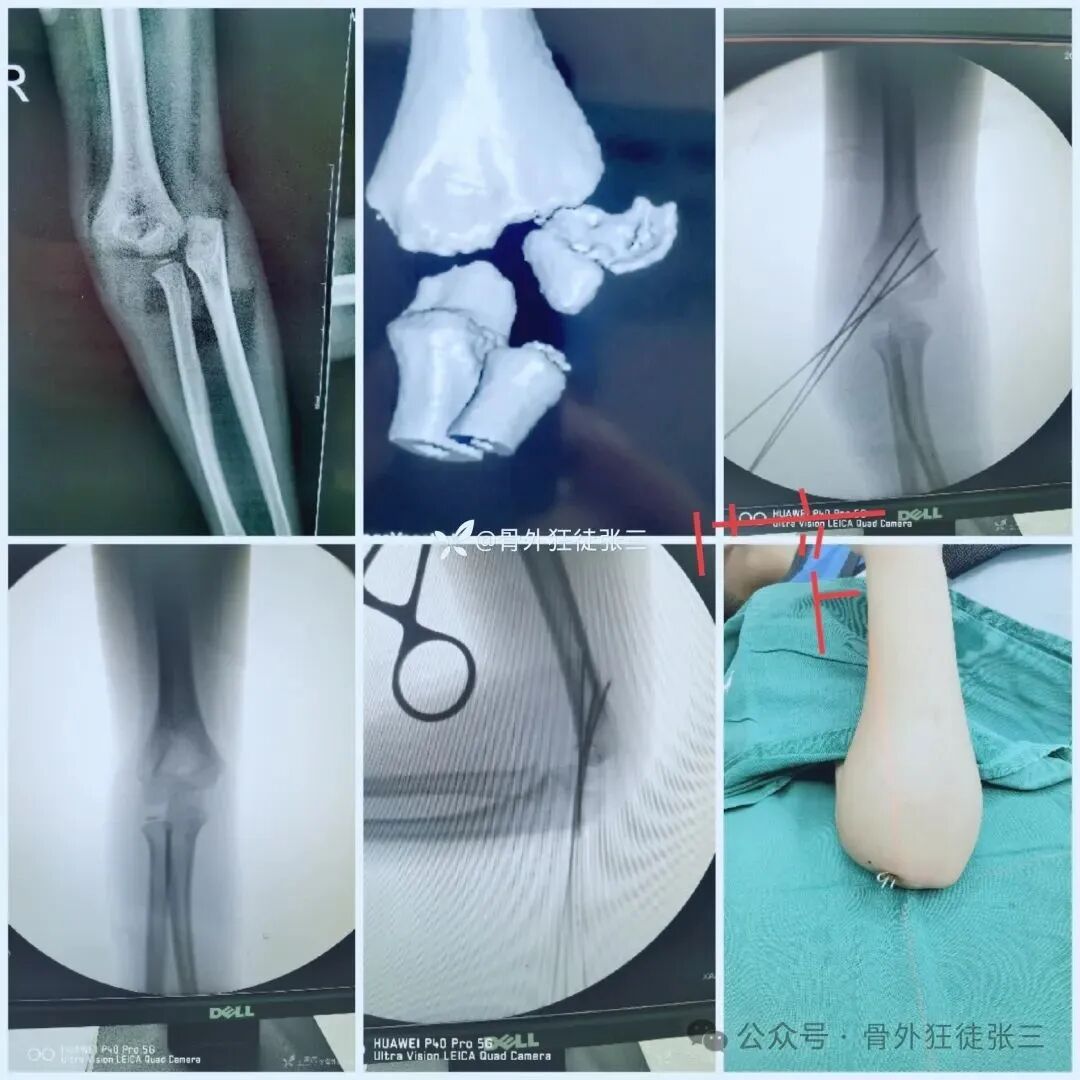

病例1:髁上骨折

桡侧三枚针发散固定

石膏固定2周,肘关节支具2周

4周复查,带针肘关节活动度正常

6周拔针

病例2,高位髁上骨折(MDJ骨折)

闭合复位,三枚针发散固定

石膏固定3周

肘关节支具锻炼3周

病例3,低位髁上骨折(全骺分离)

闭合复位,桡侧三枚针发散固定

2周石膏,2周肘关节支具锻炼

4周拔针